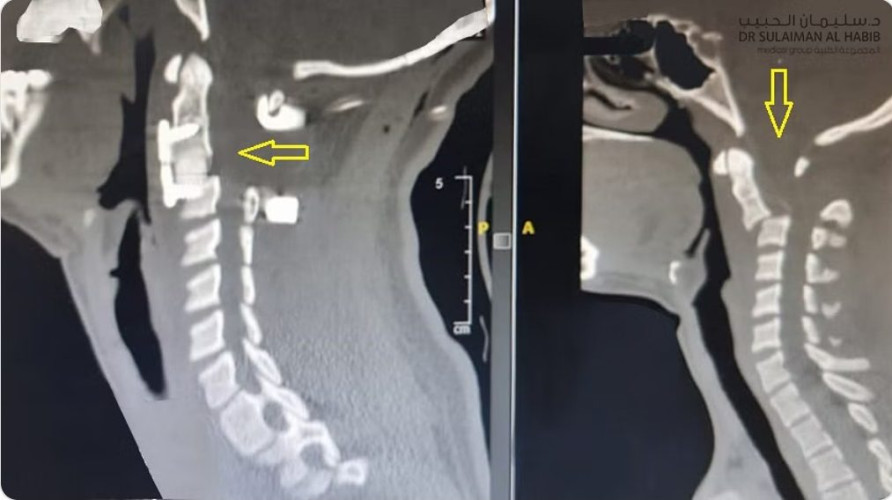

ذكر ذلك الدكتور ناجي المسعود استشاري جراحة المخ والأعصاب والعمود الفقري بالمستشفى الحاصل على الزمالة الألمانية. والذي أضاف أن الطفلة محوّلة من مستشفى آخر لم يستطع علاجها لشدة الكسور وحدّتها، ولقربها من منطقة عنق الدماغ والنخاع الشوكي؛ موضحًا أنه فور وصول الطفلة للمستشفى، تم إخضاعها للفحوصات المخبرية وأشعة الرنين المغناطيسي (M.R.I) والتصوير المقطعي (C.T Scan)، وقد أبانت النتائج وجود كسر تشابكي عكسي من النوع الانفصالي في الفقرتين الثانية والثالثة بالرقبة، كما تم رصد وجود ضغط شديد على الحبل الشوكي، الأمر الذي يفسر إصابة الطفلة بالشلل الكامل للأطراف.

وأشار إلى أنه بعد الاطلاع على كافة نتائج الفحوصات والتحاليل المخبرية، تم وضع خطة علاجية للطفلة تتم على مرحلتين؛ إجراء عملية استغرقت 3 ساعات، وتم فيها استخدام مجهر “PENTERO” المتطور وأجهزة مراقبة الأعصاب لإعادة العظم الموجود ما بين الفقرة الثانية والثالثة العنقية إلى موضعه الصحيح باستخدام الأشعة وقت الجراحة، مع إزالة الغضروف والفقرة المنكسرة وتثبيت الفقرتين من الأمام، مع إغلاق مكان الإجراء بخيوط وأدوات تجميلية. عقبها تم تحويل الطفلة للعناية المركزة للأطفال؛ حيث أكدت المتابعة الحثيثة لها والعلامات الحيوية تَحَسّنها بصورة كبيرة؛ إذ بدأت -ولله الحمد- في تحريك أطرافها العلوية والسفلية.

وقال الدكتور ناجي: بعد مرور 5 أيام على التدخل الجراحي الأول، تم استكمال الخطة العلاجية بإخضاع الطفلة للعملية الثانية، التي اتسمت بالخطورة العالية لموقعها الحساس وقربها من منطقة عنق الدماغ والحبل الشوكي ومرور بعض الشرايين الرئيسية المتوجهة للمخ، والذي يمكن أن يؤدي للوفاة لا سمح الله، وقد نجح الفريق الطبي بخبرته العالية بعد 4 ساعات وباستخدام التقنيات المتطورة، في إصلاح الفقرتين الثانية والثالثة من الخلف، ووضع براغي بالفقرة الأولى لدعم وتثبيت الفقرات (2- 3) المنكسرة، وضمان التماسك الكامل للعمود الفقري بالإضافة إلى رفع الضغط على الحبل الشوكي.